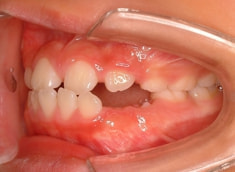

治療前

小児期ケース:反対咬合(受け口)

治療法:上顎拡大装置+フルパッシブブラケット(クリアスナップ)+フェイスマスク等